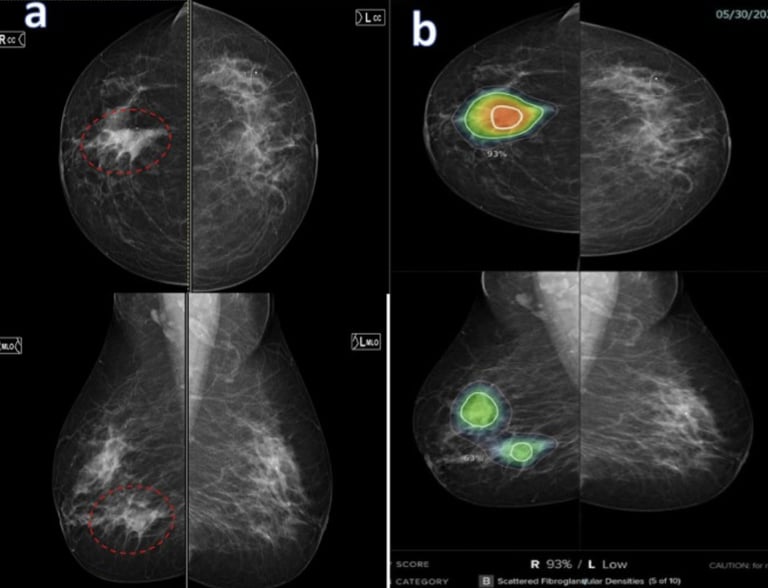

This growing popularity of AI in medicine has also raised many concerns within the medical industry, particularly in the field of medical screening. Given its efficiency and potential to advance image acquisition, medical imaging is a field that has been using AI extensively. According to an article titled Redefining Radiology: A Review of Artificial Intelligence Integration in Medical Imaging, published under the National Institute of Health (NIH), AI has technically been used pretty early on in the field of medical screening through computer aided detection (CAD) since its approval by the FDA in 1998. CAD is an advanced software that helps doctors identify potential abnormalities in mammography screenings. By improving disease detection, image segmentation, and streamlined workflows, AI integration in CAD makes cancer and disease detection more efficient.

“There are different ways that we try to address this and one of them is integrating something called ‘explainable AI.’ This tells us how the AI system came up with the interpretation that it did. But you're right, it is very hard for a breast imager to believe ai when they don't know how it came up with that interpretation. If there is a density on the mammogram, and that AI flags this density as suspicious, a radiologist may say it does not look suspicious and dismiss the finding. However, if the radiologist knew that AI came up with this density as being suspicious because there is an irregular margin and it points to where that margin is, the radiologist is more likely to believe and accept this interpretation.”